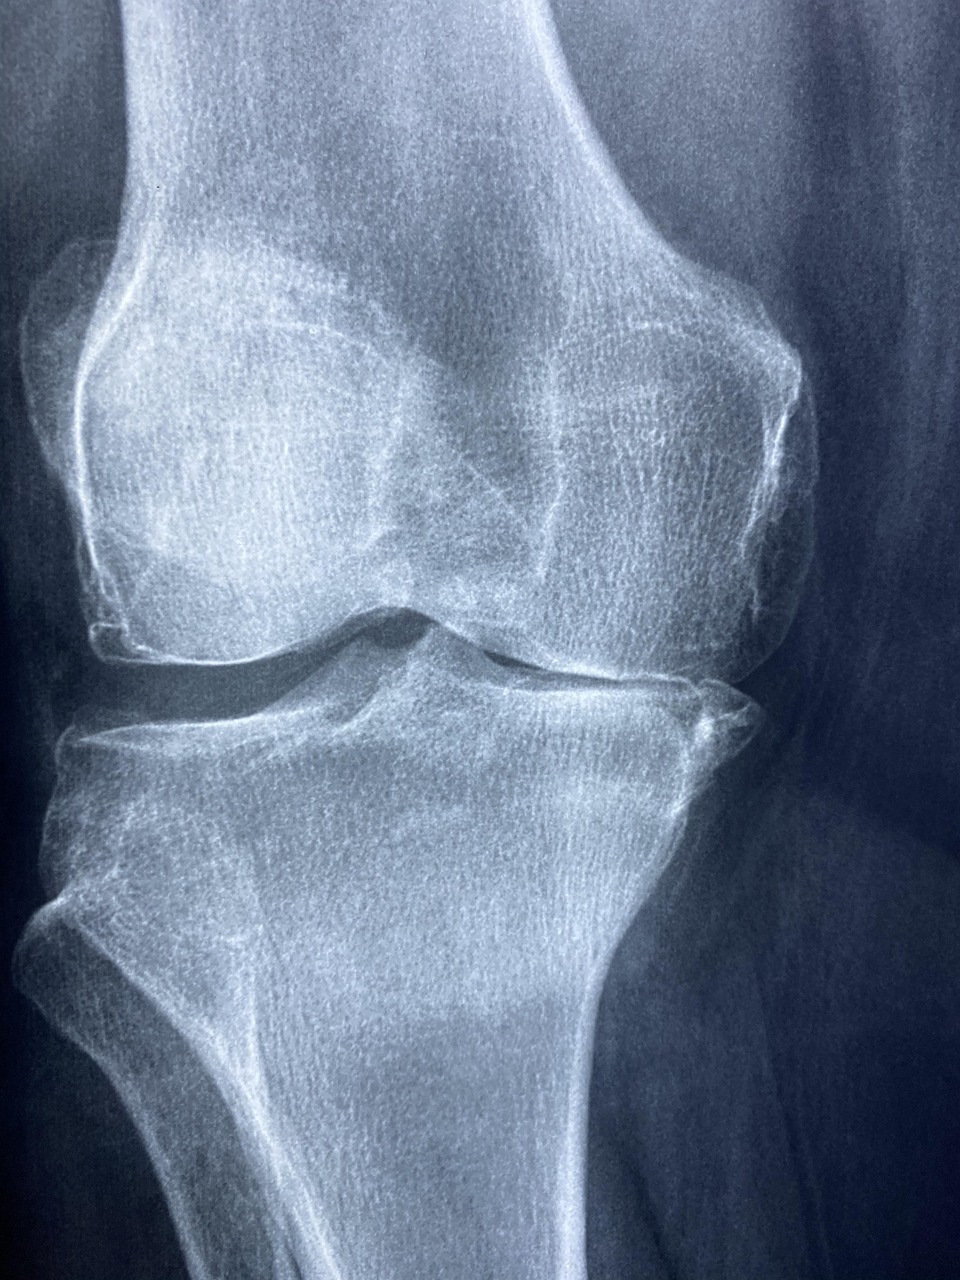

골관절염이나 고관절 점액낭염의 초기 증상일 가능성이 높습니다.

관절 내 염증이나 연골 손상이 의심됩니다.